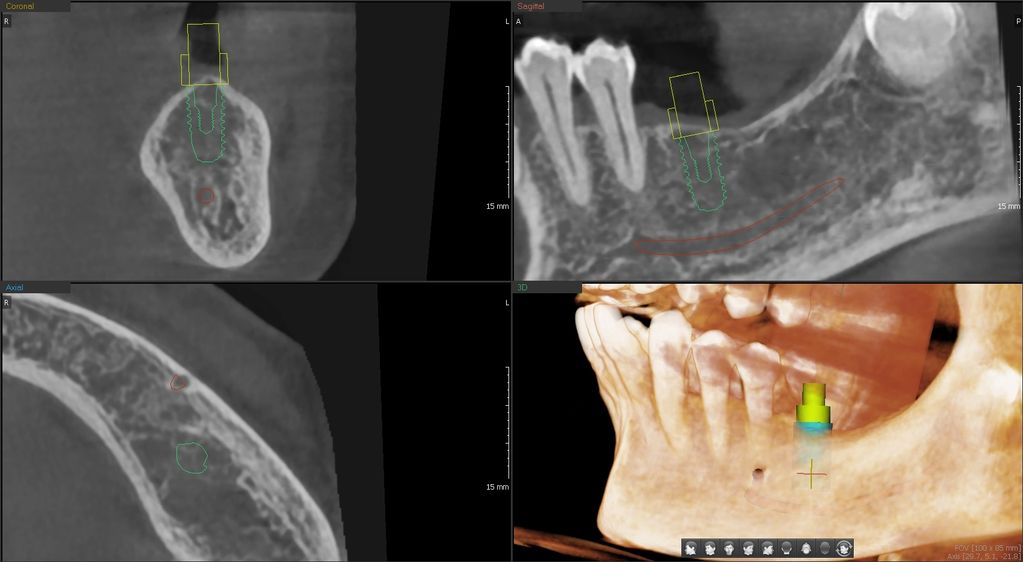

Our clinic offers CBCT (cone beam computed tomography) images to evaluate diseases of the teeth, jaw, and sinuses and also plan for implants and root canals.